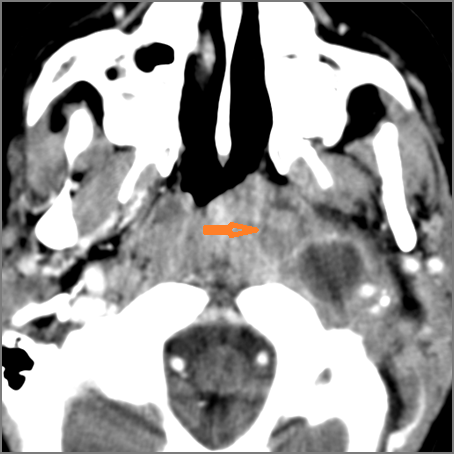

There is gas in the soft tissues.

There is evidence of active extravasation from an arterial source